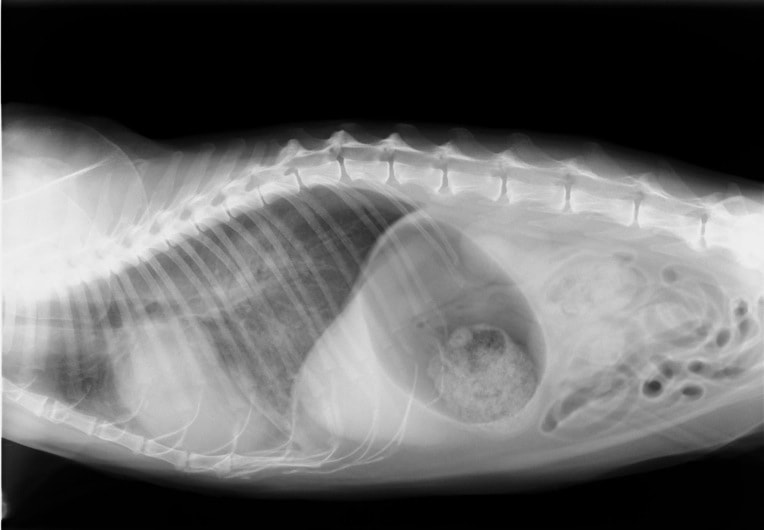

症例:【マルチーズMix 1歳齢 メス】

A:胸部レントゲン写真 正面像

B:胸部レントゲン写真 側面像

C:超音波画像 肺動脈領域の異常血流

D:左心系の拡張による二次的僧帽弁逆流

左側胸壁よりLevine 4/6の連続性心雑音が聴取された。胸部レントゲン検査において心拡大が認められ、超音波検査においても肺動脈領域に連続的な異常血流が観察された。大学病院を紹介受診され、手術が行われた。現在はACE阻害薬のみの内服で補助的治療を行っている。